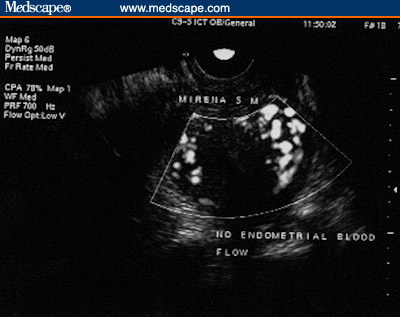

Figure 5. LNG-IUS. Subendometrial flow. (5A, 1 month

post-insertion [Note the rich flow]; 5B, 5 months post-insertion

[Note the lack of subendometrial flow]).

± 0.2 mm) (P < .0001). Subendometrial flow in the spiral artery was

significantly reduced in 35 women in group A (75%) and in none of the women in

group B (P < .0001) (Figures 4 and 5). Thus, the LNG-IUS did not